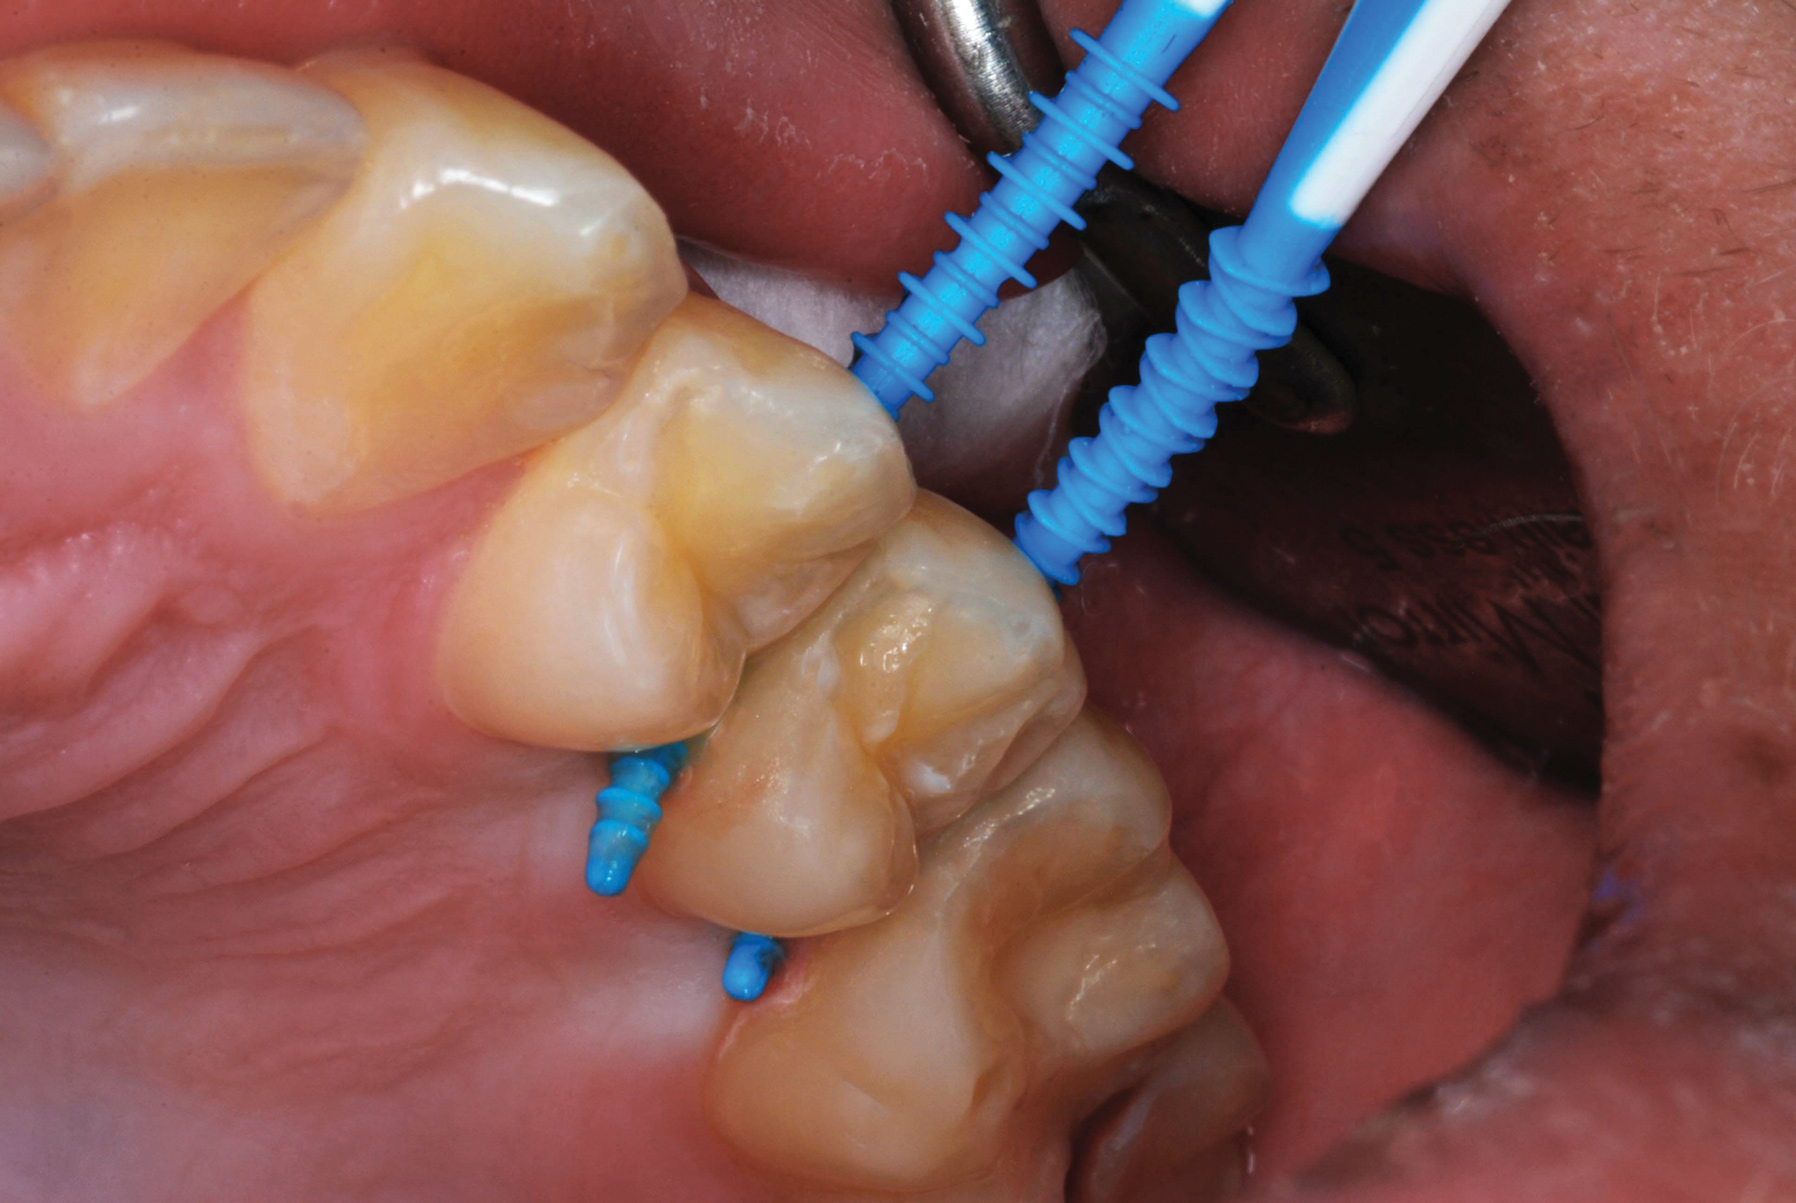

The authors' protocol for insertion of SDF-coated soft dental picks involves isolating the teeth with cotton rolls or other means, flossing the interproximal site to clear food debris and dental plaque, and then inserting a SDF-coated pick (Figure 1 and Figure 2) to saturate the contacting surfaces of the teeth with the fluid. This treatment is painless and requires no anesthetic. The pick should remain in place for at least 60 seconds and can be gently pulled in and out to agitate the fluid for enhanced surface coverage by capillary action. Additional SDF can be wiped on, using a small applicator, above the contact and in the buccal and lingual sluiceways. Excess fluid and any blood elicited may be blotted with a cotton swab. An additional 60-second insertion may be applied in the same way if there is radiographic evidence of a deeper decalcification or caries lesion. With the pick still in place, 5% (or 2.5%) fluoride varnish is painted over the treatment area, and the pick is then withdrawn.

Interproximal insertion of SDF is demonstrated in different patients in Figure 3 through Figure 11. Various diameters and brands of soft dental picks may be used depending on the closeness of the proximal surfaces and ease of insertion; for example, some picks are designed for use in wider spaces between teeth. This protocol also offers versatility. Figure 3, for example, shows the simultaneous use of three thin soft dental picks to saturate proximal surfaces with SDF in a teenaged patient; the treated regions were subsequently covered with fluoride varnish (Figure 4). This patient was initially treated in April 2019 (Figure 5), with an identical re-application 3 months later. As shown in Figure 6, the December 2019 bitewing film revealed good results with the possible exception of the contact regions of the maxillary first and second molars. New SDF application was completed in the December appointment.

Fig 7. An example of the use of thicker picks for premolar interproximal sites.

Figure 7